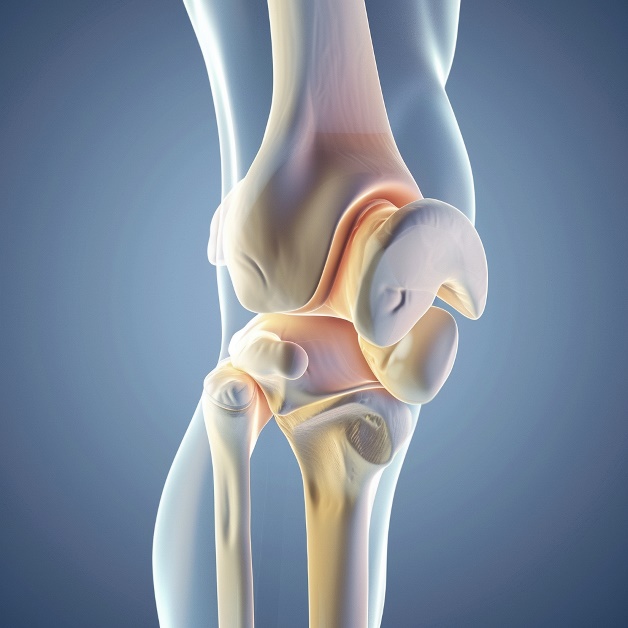

KNEE ARTHROSCOPY

Knee arthroscopy is a minimally invasive surgical procedure used to diagnose and treat a range of knee issues, offering quicker recovery times and less postoperative pain compared to traditional surgery

KNEE CARTILAGE REPAIR OR RESTORATION SURGERY

Knee cartilage repair or restoration surgery aims to treat damaged cartilage and promote healing, helping to restore joint function and reduce pain for improved long-term knee health.